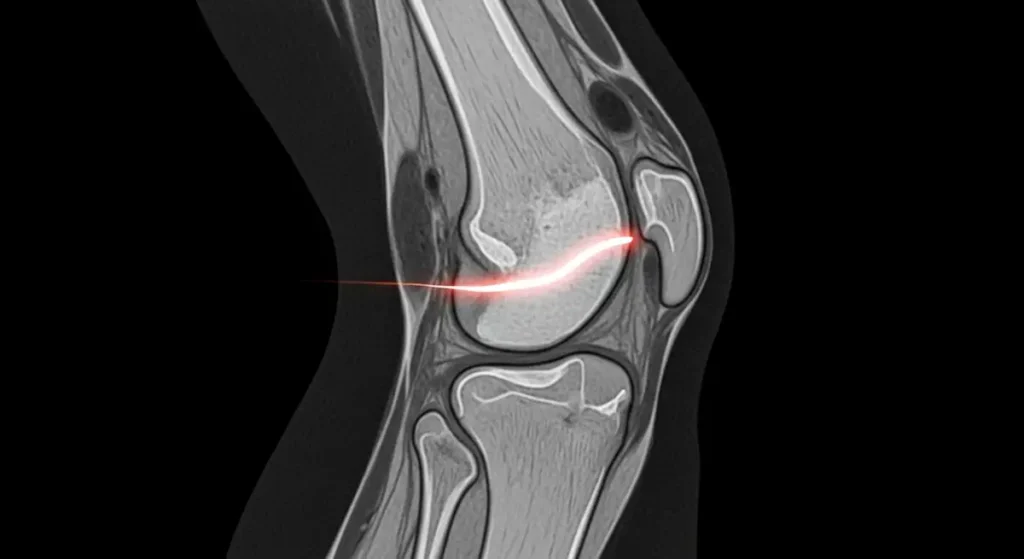

A ressonância magnética detecta sinais da lesão de menisco tipo rampa, porém, o padrão ouro é a artroscopia diagnóstica, que permite inspeção direta da região póstero medial, inclusive com exploração do recesso meniscocapsular.